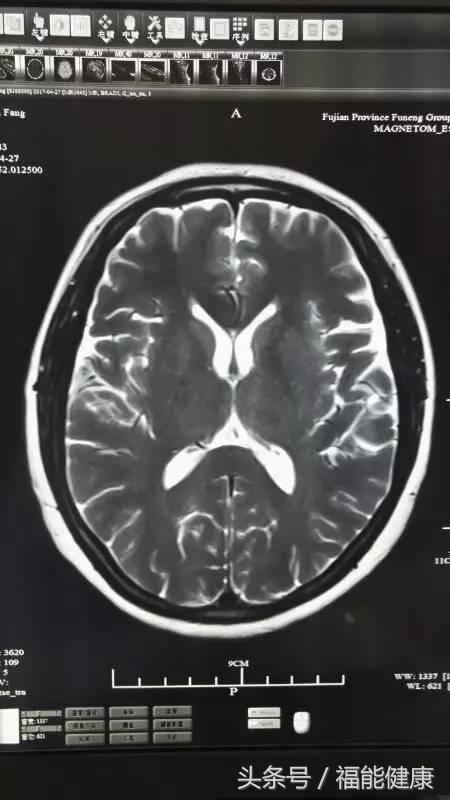

据福能健康管理中心放射影像科主任郑章和介绍,核磁共振对脑、甲状腺、肝、胆、脾、肾、胰、肾上腺、子宫、卵巢、前列腺等实质器官以及心脏和大血管以及骨关节都有很好的诊断功能。核磁共振的原理实际上是,将人体置于特殊的磁场中,用无线电射频脉冲激发人体内氢原子核,引起氢原子核共振,并吸收能量。在停止射频脉冲后,氢原子核按特定频率发出射电信号,并将吸收的能量释放出来,被体外的接受器收录,经电子计算机处理获得图像,这就是核磁共振成像的基本原理。

郑主任谈到,许多人对核磁共振检查的认识是有误区的。实际上,核磁共振是磁场成像,没有放射性,对人体无害,非常安全,这是核磁共振的优势之一。此外,核磁共振在发现病变及发现肿瘤方面也是一把好手,与其他辅助检查手段相比,核磁共振具有成像参数多、扫描速度快、组织分辨率高和图像更清晰等优点。

核磁共振检查不仅可以早期发现某些肿瘤、脑梗塞、脑出血、脑脓肿、脑囊虫症及先天性脑血管畸形,还能确定脑积水的种类及原因等。通过对头部及心脏等部位的核磁检查,在身体健康尚未发出红灯警讯前,早期发现心脏病、脑梗等高风险疾病隐患。当然,MR检查也不是万能的,在很多情况下也需要结合DR、超声、CT等手段,互为补充。同时,在诊断疾病的时候,尚需要密切结合临床其他资料。